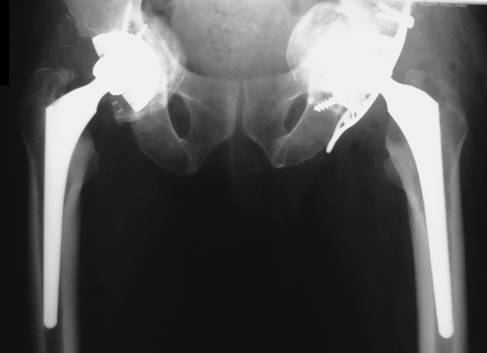

Artroplastiile s-au realizat in doua interventii operatorii la distanta de 6 luni, initial pe partea dreapta (fig. 2), unde s-a instalat initial decompensarea algica si apoi pe partea stanga (fig. 3), unde a fost necesara crearea unui nou fund al acetabulului cu ajutorul unui inel de ranforsare insurubat tip Brch-Schneider. Intre inel si acetabul s-a introdus o grefa osoasa cortico-spongioasa recoltata din creasta iliaca. Pe ambele parti, componenta femurala a fost de tip necimentat.

Fig. 3. Rezultat final la 1 an postoperator.